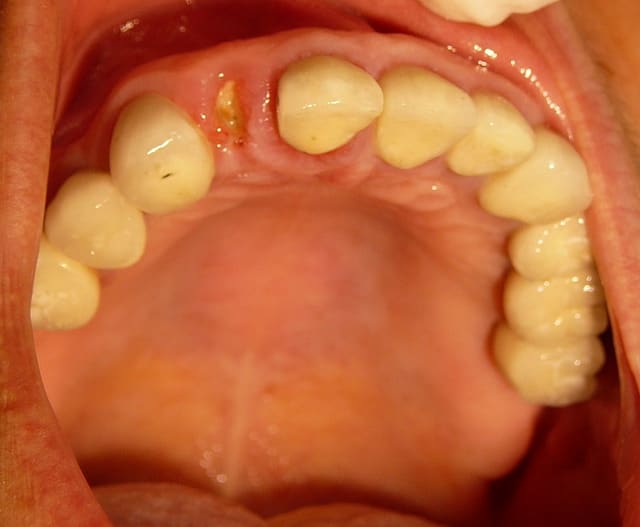

Dans le cas présenté, les images sont sur-exposées, couleur fade.

Avec un parodonte épais comme celui-ci, former la gencive n'est pas trop difficile.

With a gum biotype like this on, manipulating the gum is not very difficult.

Il y a aussi un gummy-smile et un sourire inversé, dommage après tant de couronnes.

The final result is a gummy smile with reverse smile line...too bad after all those crowns. A simple perio surgery could have give better result.